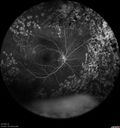

20 year old mane with fresh vitreous hemorrhage in the right eye. At age 15 he had a PPV and laser in the left eye and laser in the right eye. The vision is OD 20/80 PH 20/25, OS 20/25. The left eye has a mild cataract. He had prior testing for coagulopathies which was negative. Testing done for syphillis and TB was negative. Additional laser was done to prevent further bleeding in the right eye.